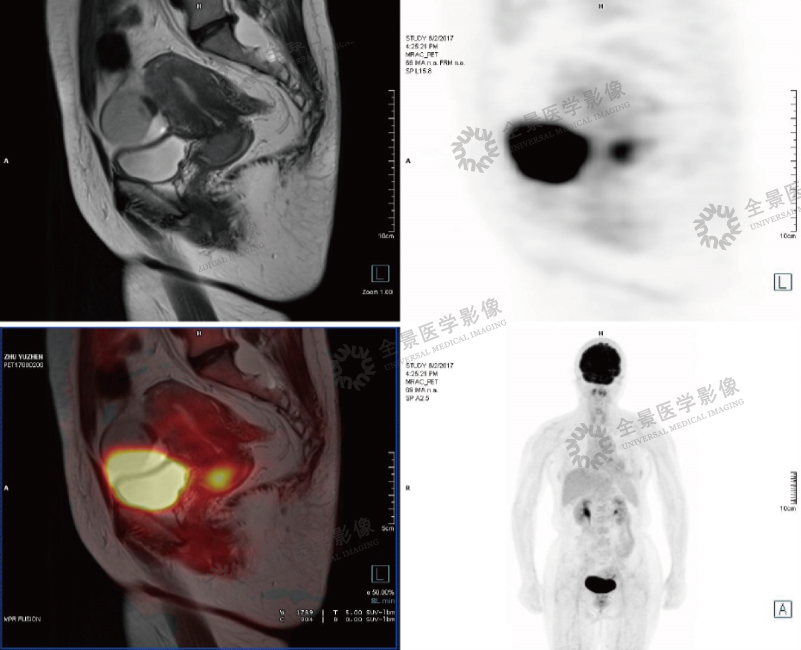

案例2:中年女性,下腹部坠胀感1个月。宫颈可见一类圆形软组织信号,大小约2.3cm*2.5cm,FDG摄取增高。

结论:病理诊断为宫颈鳞状细胞癌。PET/MR对子宫、卵巢显示优于PET/CT,可清晰病灶大小,形态及周围浸润情况。